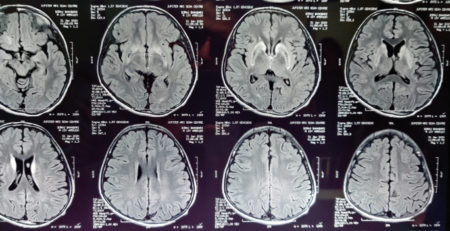

5years old boy with normal development history came with features of altered sensorium and frequent seizures. He went into status epilepticus requiring multiple antiepileptic medications and was ventilated for 7 days. His MRI brain and spine was suggestive of acute disseminated encephalomyelitis(ADEM). The antibodies for NMOSD(NMO and anti-MOG antibodies) were negative.He was treated with injection methylprednisolone and IVIG(immunoglobulin). Now after discharge he has become as normal as before.